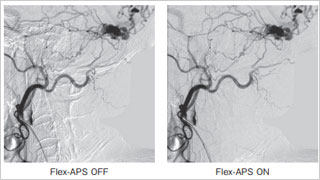

Trinias在脑动脉瘤弹簧圈栓塞术中的性能

德洲会 名古屋德洲会综合医院 脑神经外科

天野 贵之